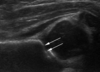

Q

A

labrum